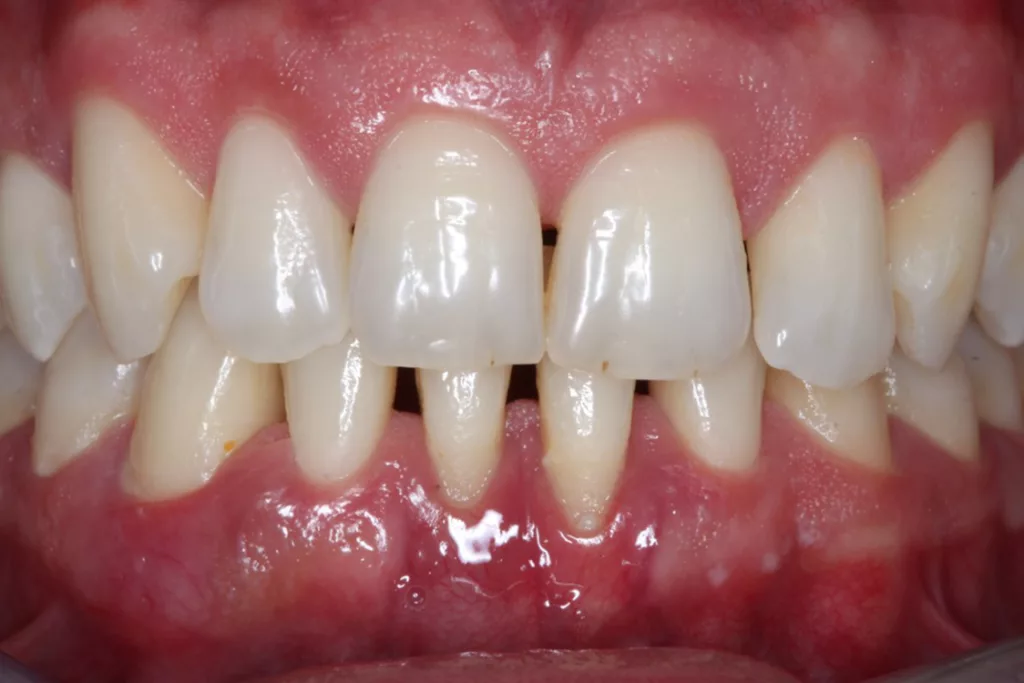

Parodontale Erkrankungen sind multifaktorielle, chronische Krankheiten. Die wesentliche Voraussetzung für Entstehung und Progression einer Parodontitis ist eine (meist) polymikrobielle opportunistische Infektion mit pathogenen Mikroorganismen des oralen Biofilms [1]. Dabei wirken die Bakterien nicht nur direkt; eine entzündliche Reaktion des Parodontiums wird vielmehr auch ohne eine bakterielle Invasion in die entsprechenden Kompartimente des Zahnhalteapparates durch die Immunantwort des Wirts auf den bakteriellen Reiz hervorgerufen [53]. Vor dem Hintergrund dieses pathogenetischen Verständnisses parodontaler Erkrankungen werden in dieser Arbeit nun wissenschaftlich basierte und praxisnahe Empfehlungen für die tägliche Mundhygiene (Abb. 1) herausgearbeitet.

Für die regelmäßige Reinigung der Zähne stehen heute verschiedene Hilfsmittel zur Verfügung (Abb. 1). Darunter finden sich manuelle und elektrische Zahnbürsten, konzipiert in erster Linie für die Säuberung oraler, bukkaler und okklusaler Zahnflächen, sowie Instrumente und Geräte für die Reinigung der Zahnzwischenräume, wie Zahnstocher, Zahnseide, Superfloss, Interdentalraumbürstchen oder auch Mundduschen [20]. Vor allem die Interdentalraumhygiene stellt für viele Patienten/-innen ein Problem dar und Karies sowie Parodontitis etablieren sich daher bevorzugt an den Zahnflächen der Zahnzwischenräume [24–27]. Nur wenige Patienten/-innen zeigen allerdings die manuelle Geschicklichkeit und Compliance, um technisch anspruchsvolle Produkte wie beispielsweise Zahnseide und Interdentalraumbürstchen oder eine entsprechend instruierte Putztechnik auch wirklich vernünftig anzuwenden [28]. Für körperlich oder mental eingeschränkte Patienten kann die adäquate Reinigung der Zähne auch nahezu unmöglich sein.

Robuste Evidenz aus aktuellen großen bevölkerungsbasierten Studien zeigt eine Überlegenheit der Effektivität elektrischer Zahnbürsten gegenüber Handzahnbürsten. Darüber hinaus legen systematische Übersichtsarbeiten und In-vitro-Studien einen zusätzlichen Effekt – die Putzwirkung auch ohne direkten Borstenkontakt durch unterschiedliche Strömungsphänomene – bestimmter elektrischer Zahnbürsten (Schallzahnbürsten) nahe. Laboruntersuchungen zeigen aber auch große Unterschiede der untersuchten Zahnbürsten hinsichtlich der Effektivität der Biofilmreduktion. Das bedeutet, dass in der Klinik (Abb. 7–9) in aller Regel eine Empfehlung für elektrische Zahnbürsten und (!) geeignete Hilfsmittel für die Zahnzwischenraumpflege vorliegen sollte.